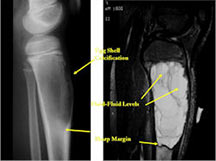

MRI/CT:

- Fluid-fluid levels secondary to cystic cavities filled with blood products. The sediment from blood products settle to the gravity dependent area of the cavity and the fluid component floats to top thus forming a fluid-fluid level.

- MRI and CT are also useful for demonstrating the local extent of the tumor and any soft tissue mass

- CT also useful for demonstrating scant osteoid production

- ABC usually has more sharply defined margins

- ABC usually has peripheral “egg shell†calcification indicating that the periosteum is intact around the soft tissue component (a benign radiographic feature)